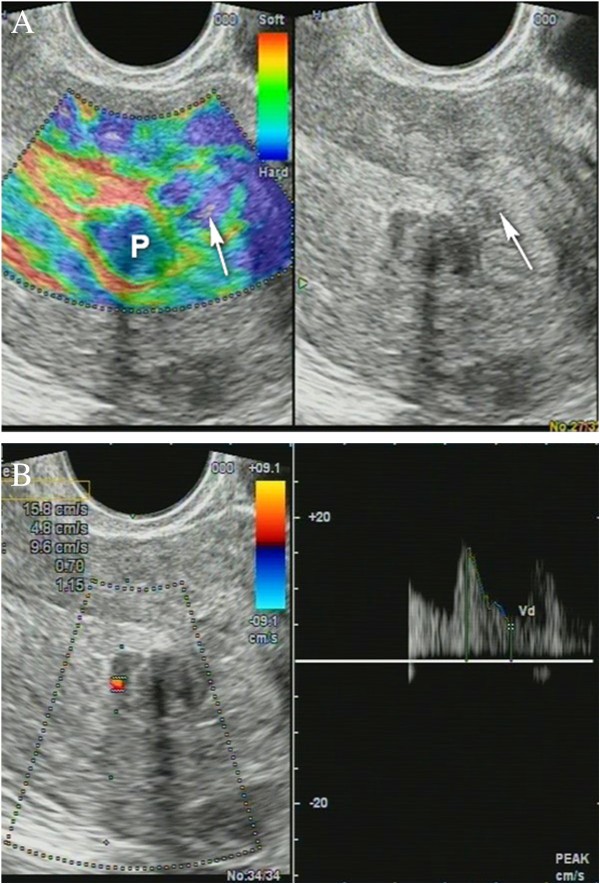

Non-homogenous and irregular margins were significantly higher in AEH than in both groups (P < 0.01). Mean M-echo thickness was found to be non-significant. Hypoechoic areas, hypervascularity on Doppler imaging, and stiffness (Figures 14 and 15) were more specific for AEH than for glandular cystic hyperplasia (P < 0.01, P < 0.01, P < 0.01, respectively; Figure 16). Fluid in the uterine cavity and BGR artefact were found to be specific for AEH (P < 0.01; Figure 17); BGR appearance correlated to the presence of fluid in the uterine cavity (r > 0.97; Figure 18).

Figure 14

Endometrial polyp ( P ). (A) Stiff polyps on SEG, arrow indicates invisible polyp in grey scale that was detected on SEG; (B) Dopplerography of polyp vessel, RI = 0.7.

Figure 15

Sonoelastography of endometrial lesion. Soft pattern on SEG helps to exclude the polyp.